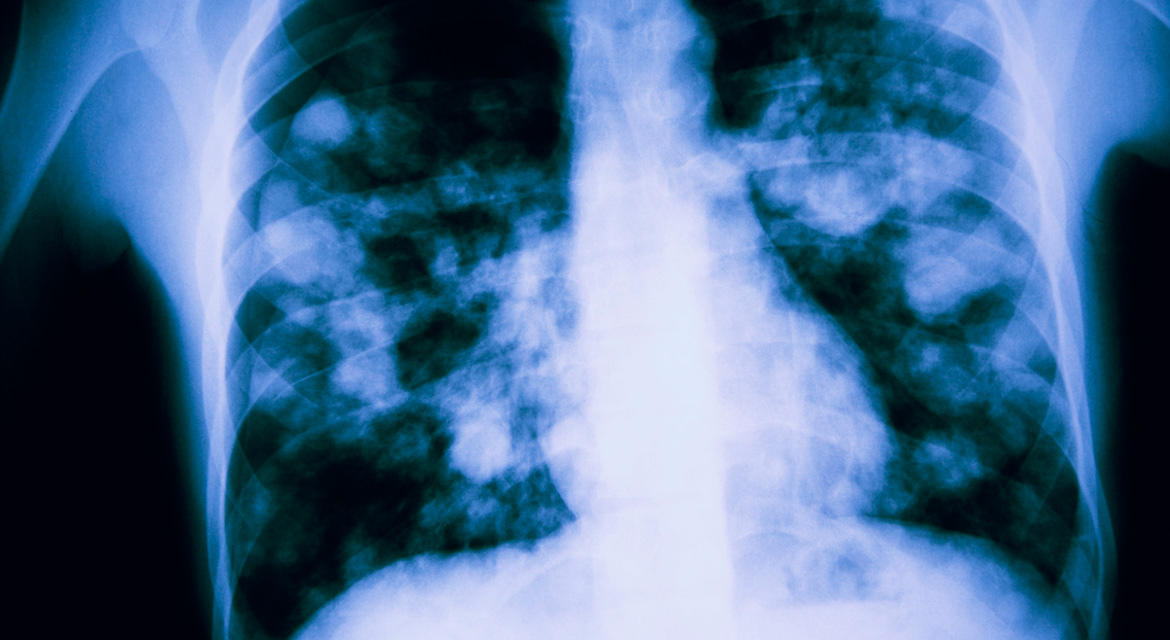

Neumonía

La neumonía, conocida popularmente por el nombre de pulmonía, es una inflamación del pulmón o de una parte de él producida generalmente por la bacteria neumococo, aunque también puede producirse por el virus sincitial respiratorio o por hongos. El día 12 de noviembre de cada año se celebra el Día Mundial contra la Neumonía, una iniciativa promovida por la Coalición Mundial contra la Neumonía Infantil que intenta concienciar a la población del peligro que puede llegar a suponer esta enfermedad. Para colaborar a este fin, os mostramos algunos datos sobre la enfermedad:

Se trata de una infección respiratoria que, entre sus síntomas, provoca inflamación y enrojecimiento del tejido pulmonar, dificultando y haciendo más dolorosa la respiración. Además suele conllevar tos con moco sanguinolento, dolor torácico, sudores nocturnos, fiebre, escalofríos o pérdida de peso. El rápido diagnóstico es vital para que no se convierta en una enfermedad grave y mortal.